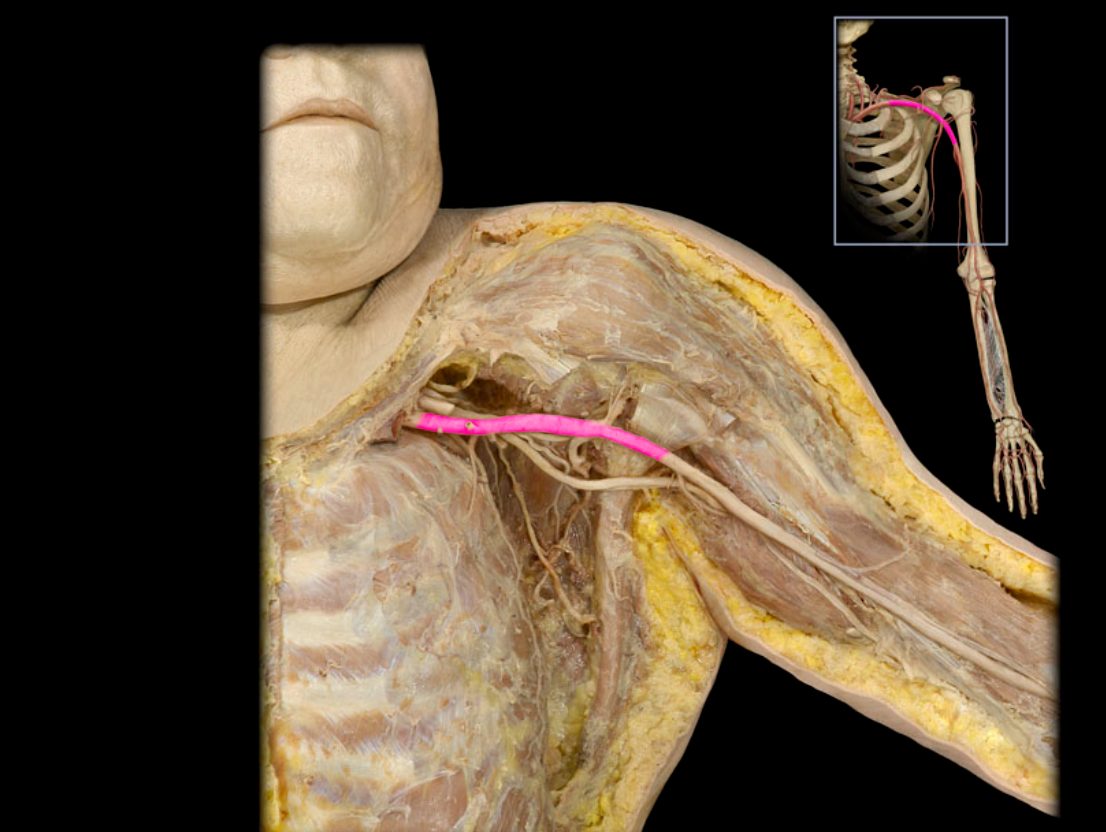

Axillary a.

Brachial a.

Subclavian v.